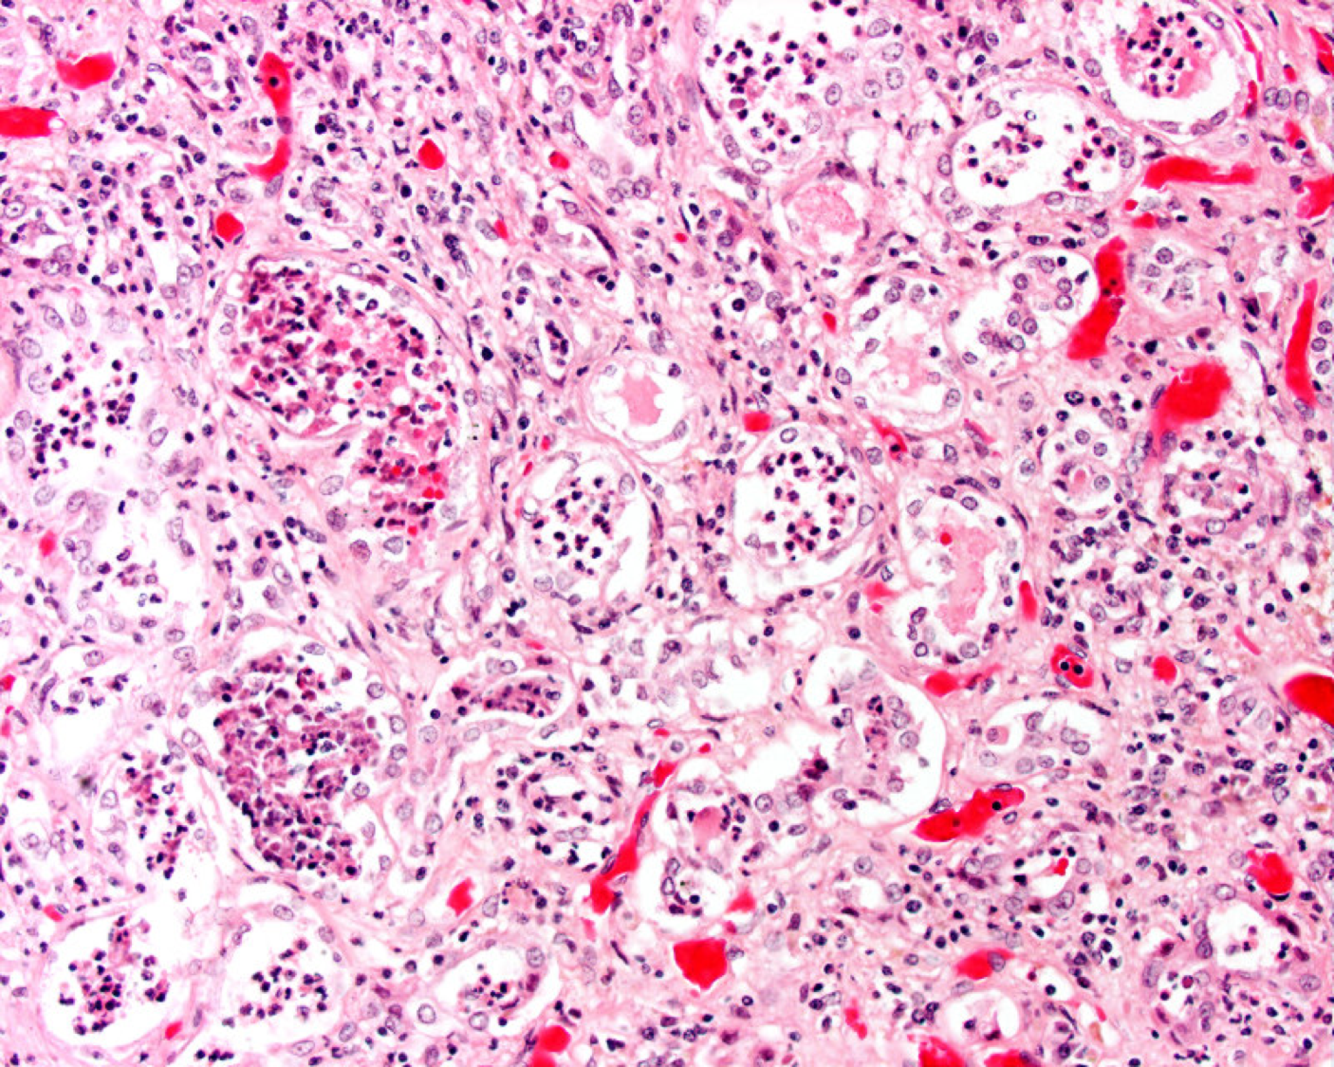

What do you see? diagnosis?

Bunch of neutrophils hanginging out

pyelonephritis